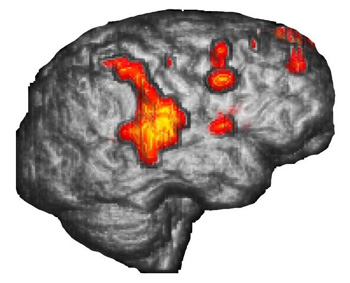

Surface Rendering

Surface rendering is a computer post processing method that removes the skin and the skull to allow us to see the brain surface. The anatomy of gyri and sulci are displayed in the same way the neurosurgeon sees the brain. Functional maps can be superimposed on these images. Some activation may take place deep in the sulci which may be presented on these images bleeding through the cortical surface.

Case 1

Right handed 15 year-old-boy with intractable epilepsy performing a verbal "repetition task." The surface rendition beautifully depicts the activation occurring in the posterior third of the right superior temporal gyrus and extending toward supramarginal gyrus and Brodmann's area 7. The areas of activation are better displayed than with conventional 2D MR images.